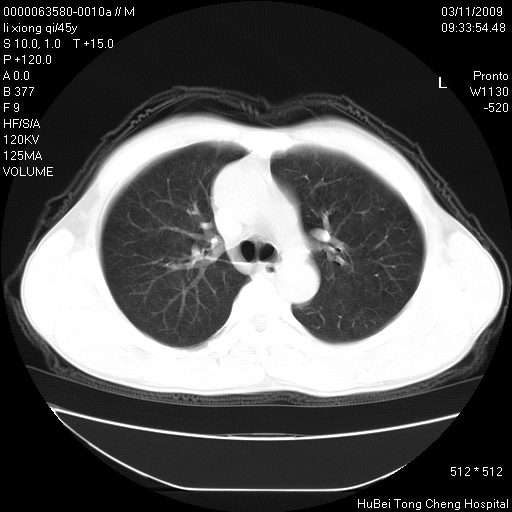

患者 男,45岁。胸痛,咳嗽伴痰中带血1月余。

临床诊断:肺结核?

胸部ct轴位平扫(层厚10mm,螺距1.5,重建间隔10mm),图像如下: